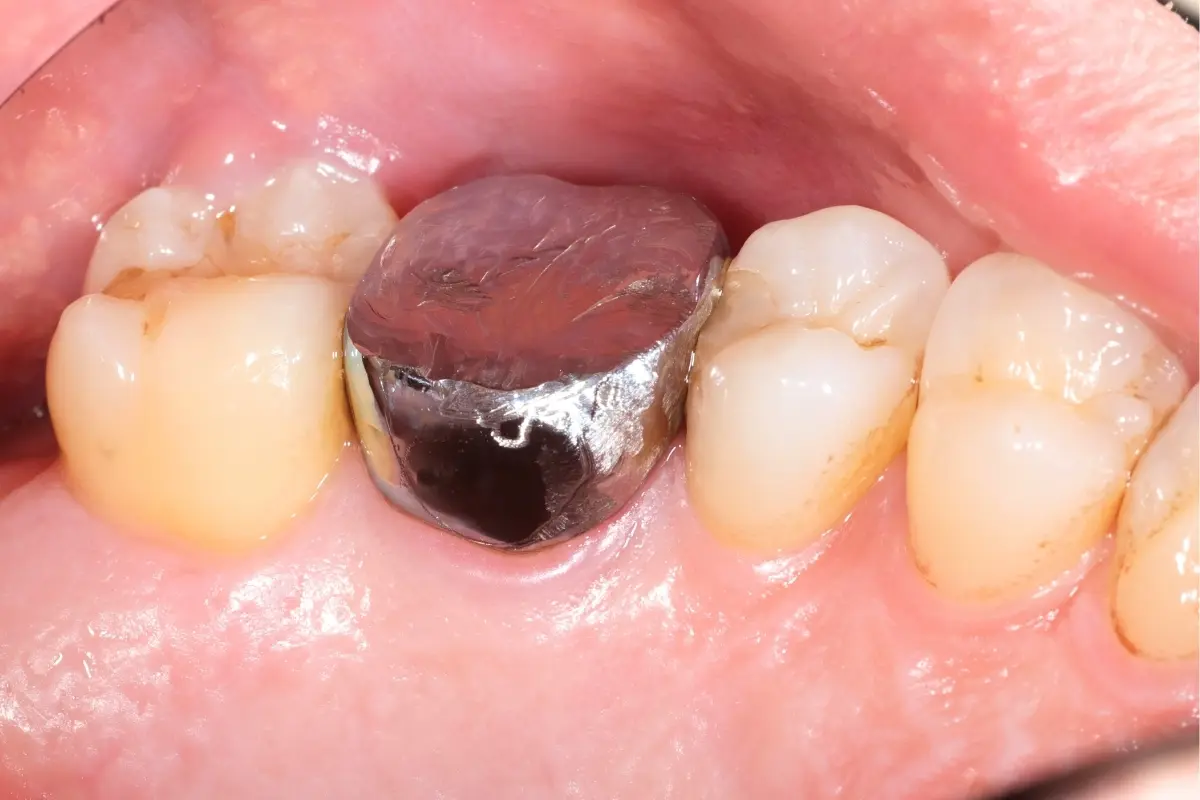

• 術前 12

術後 12

人工植牙

主治醫師

• 林明志

治療時間

約一年

主訴

左上假牙外側反覆長膿胞,想尋求治療方法